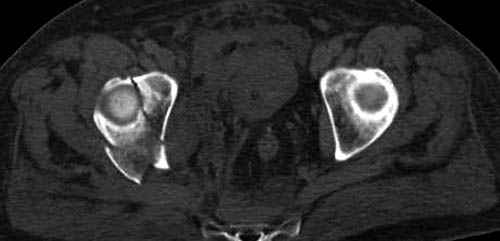

Дополнительно имеется перелом ацетабулума: задняя

колонна с полупоперечным переломом, и переломы костей лица.

На седьмой день зафиксирован перелом ацетабулума через задний доступ. Перед операцией для профилактики DVT, IVC фильтер, также получает Lovenox.

По возможности вышлите снимки, сканы таза до

реконструкции, интраоперационные.

По снимку создается впечатление о высоком поперечном переломе, задней колонны, стенки; почему не пользовались *magic screw*?

Там множество обычных 2.7 мм шурупов, потом идет фиксация основными пластинами.

Снимки здесь....